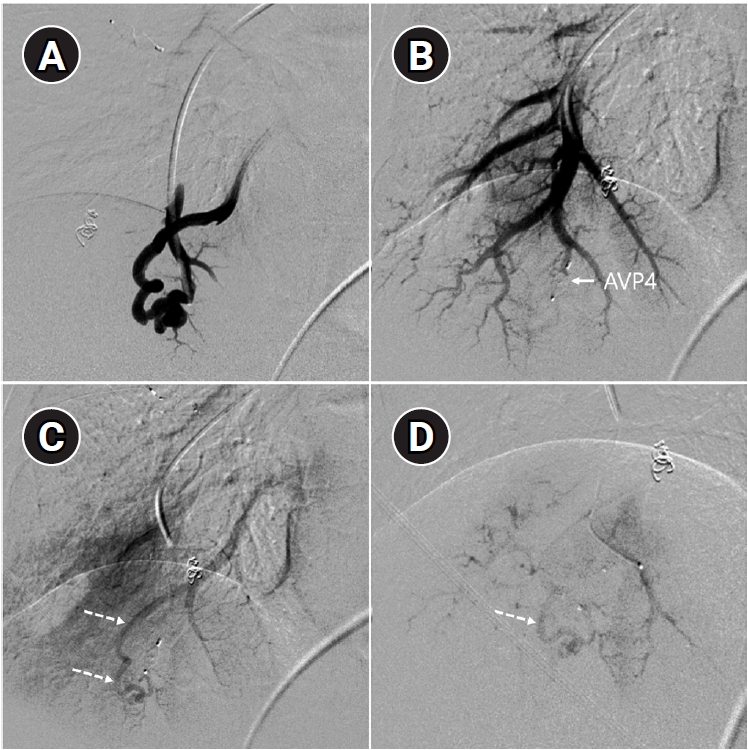

Fig. 7.

Example of a patient showing reperfusion after pulmonary arteriovenous malformation (PAVM) embolization using an Amplatzer vascular plug type IV (AVP 4). (A) Angiography of a simple-type PAVM in the right lower lobe accessed with a 5-Fr catheter. (B) Early pulmonary arterial phase image from a diagnostic angiography performed three years later due to suspected reperfusion on follow-up computed tomography, showing that the pulmonary vein is not visible distal to the AVP 4 (indicated by the arrow). (C) Delayed phase image confirming the pulmonary vein, marked by dashed arrows, which corresponds to the venous sac and draining vein seen in (A), now reduced in size. (D) A typical example of reperfusion shown on angiography using a microcatheter in an adjacent pulmonary artery, illustrating multiple newly formed tortuous collaterals leading to the draining vein (marked by dashed arrows). In this patient, additional AVP 4 embolization was performed at the tip of microcatheter (black arrow). However, draining vein size persisted even after additional treatment (not shown).

kjir-2026-00010f7.jpg

Long-term follow-up after treating PAVMs is needed to detect newly developed PAVMs and to identify persistence or recurrent flow [10,11]. Treatment failure in PAVMs can be classified as recanalization and reperfusion. Recanalization refers to the reopening of blood flow through spaces between the previously placed embolic material (Fig. 6). Reperfusion, on the other hand, occurs when blood flow from an adjacent pulmonary artery reopens the previously embolized distal vein or venous sac (Fig. 7) [32]. As the primary follow-up modality, CT is recommended, but there are currently no specific guidelines on whether or not to use contrast enhancement [33]. It is recommended to perform an initial evaluation by CT about 6 months after PAVM embolization, and then follow-up with CT every 3–5 years thereafter (Fig. 8). In CT follow-up, the evaluation is based on the reduction rate of the venous sac or the draining vein, and the traditional criterion is that there should be at least a 70% reduction in the size of the venous sac or draining vein [34,35]. In recent studies, there have been opinions that this 70% size reduction criterion is too strict. In response, some research using angiographic-confirmed cases or time-resolved magnetic resonance angiography (TR-MRA) has proposed a 50%–60% guideline [36,37]. When using CT, repeated radiation exposure and metal artifacts from the coils can be problematic. By using metal artifact reduction techniques, it is possible to obtain clear images of the surrounding parenchyma, and this also helps in assessing parameters like the draining vein diameter reduction rate (Fig. 9) [38]. Furthermore, low-dose CT protocols may help reduce cumulative radiation exposure during repeated follow-up imaging.